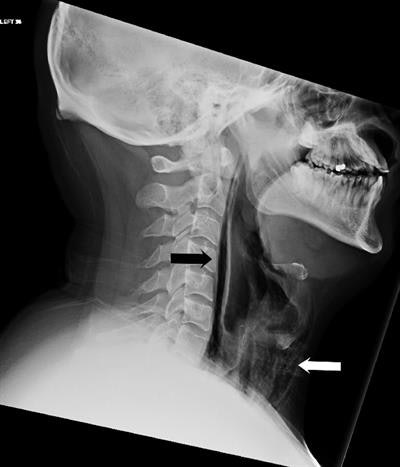

A lateral soft-tissue neck radiograph was performed, followed by an urgent, contrast-enhanced CT of the neck and thorax that confirmed the presence of extensive soft-tissue emphysema and pneumomediastinum.